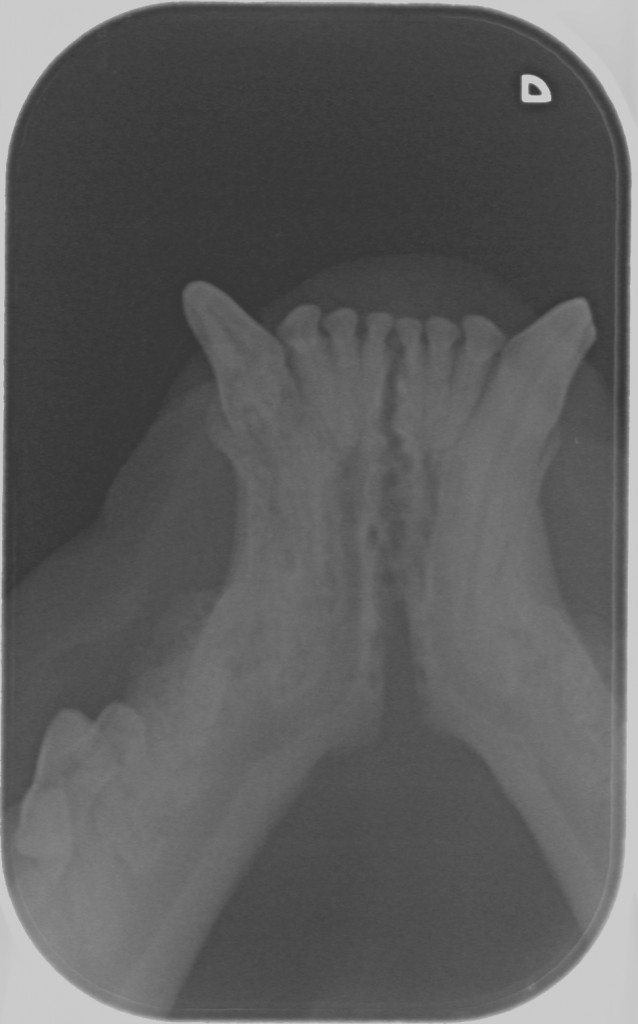

Tænder med TR skal trækkes ud. Men alligvel er det nødvendigt at tage tandrøntgen af alle tænderne for at se om der er andre tænder, der er angrebet af TR.

Det eneste man som katteejere kan gøre er at få sin kat undersøgt for TR mindst en gang årligt i forbindelse med det årlige tjek hos dyrlægen. Din dyrlæge kan henvise til speciallæger, der foretager tandrøntgen, men du kan også selv henvende dig til en specialdyrlæge, der foretager tandrøntgen af katte.

På Dyretandspecialist kan du læse mere om sygdommen Tooth Resorption (TR/FORL) hos katte. Her kan du både se røntgenbilleder og billeder af tandsygdommens stadier, samt se symptomerne på sygdommen, så du ved, hvad du skal være opmærksom på hos din kat.

Nedenfor kan du se de 8 røntgenbilleder af Shana-Mio´s tænder, som specialtanddyrlægen tog af hendes tænder i 2008, da hun fik konstateret TR/FORL: